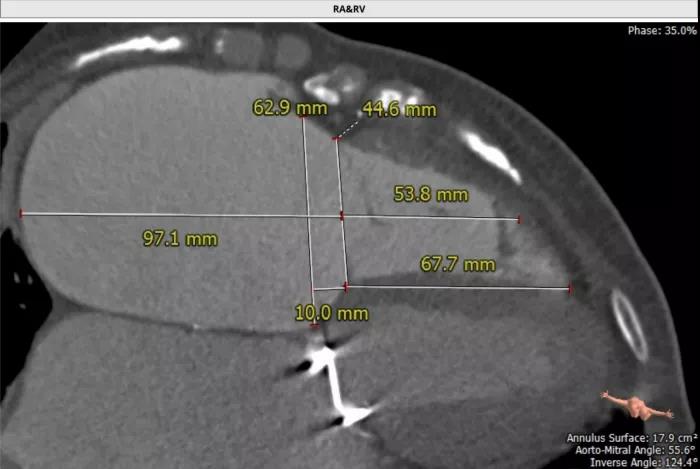

海军军医大学附属长海医院心血管外科徐志云、陆方林团队分享的患者为68岁女性,14年前接受了“二尖瓣机械瓣置换术”,7年前出现活动后胸闷气喘,伴双下肢水肿,后体检发现三尖瓣重度反流,并逐渐加重,超声显示三尖瓣瞬时反流量达88ml。由于患者还伴有房颤等多种合并症,外科手术风险极大。长海医院心外科徐志云、陆方林团队综合CT、超声检查结果,对该患者的病情进行了充分的评估,采用JS/TTVI-30-55型号的LuX-Valve®瓣膜系统对患者进行微创治疗。

当天下午,首都医科大学附属北京安贞医院心外科周玉杰、张海波团队紧接着长海医院,分享了第二例LuX-Valve®手术直播。手术病人是55岁的女性,11年前因风湿性的心脏瓣膜病接受了主动脉瓣及二尖瓣机械瓣置换。最近3年出现乏力、疲劳、外周水肿,彩超提示“重度的三尖瓣反流,右心功能不全”。孟旭、张海波团队经过术前评估后,采用JS/TTVI-28-55型号的LuX-Valve®瓣膜为该患者进行经导管三尖瓣置换术。手术也顺利地完成,瓣膜固定稳定,并有效地消除了三尖瓣反流。术中,安贞医院周玉杰院长和张海波教授再一次详细介绍了操作过程及细节,并解答了参会嘉宾的提问。云端各位专家给予LuX-Valve®瓣膜及手术团队高度评价,并希望LuX-Valve®经导管三尖瓣置换系统能早日正式进入临床,造福广大三尖瓣关闭不全患者。